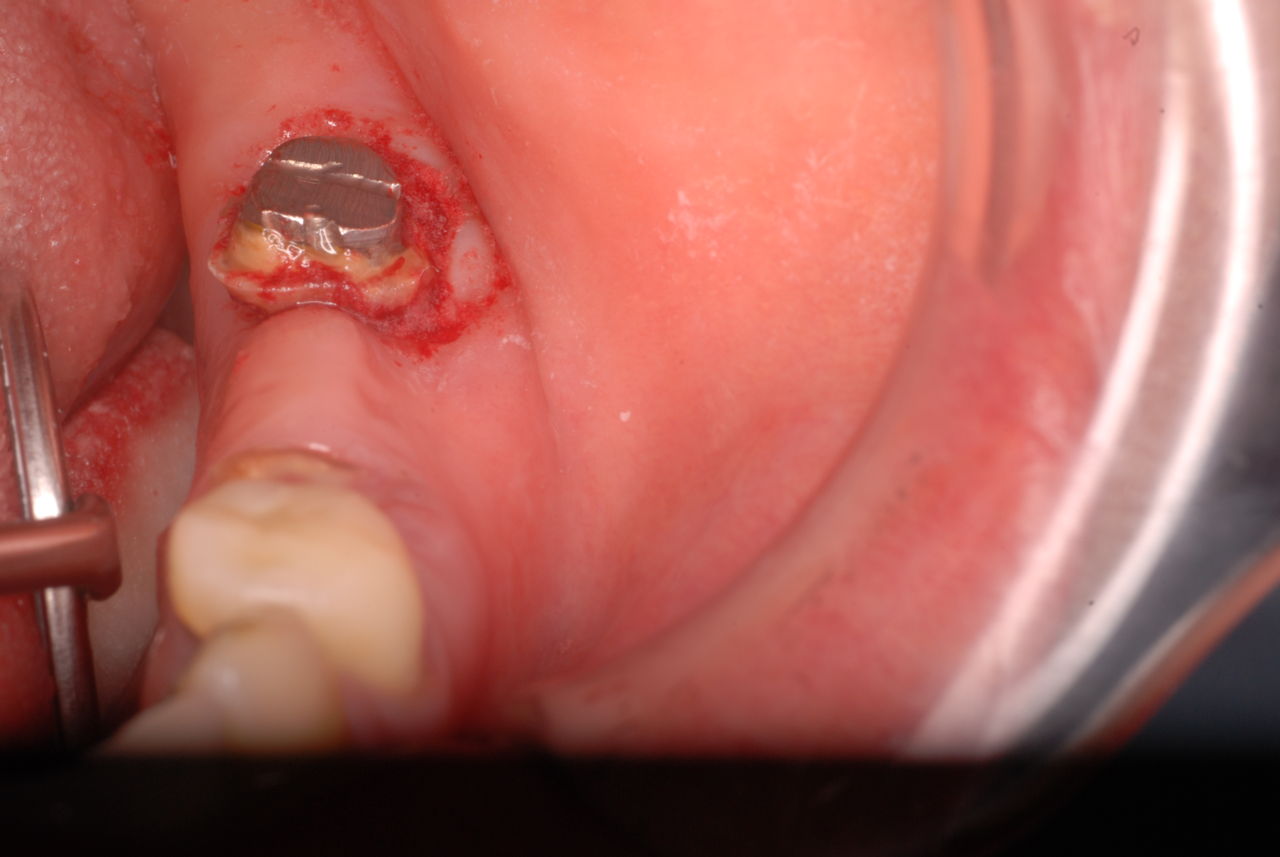

写真は典型的な取り残したまま銀歯を入れていた方のものです。よくぞ痛くならなかったものです。

意外と手間取り一時間以上かかりセメントを入れてとりあえず終了いたしました。神経が近いので傷つけて損傷すると助かる見込みが少なくなり、痛みが出て死んでしまうとか膿んでしまうこともあるのです。![570b1c06-s[1]](https://livedoor.blogimg.jp/netdental/imgs/6/0/60221eb2.jpg)